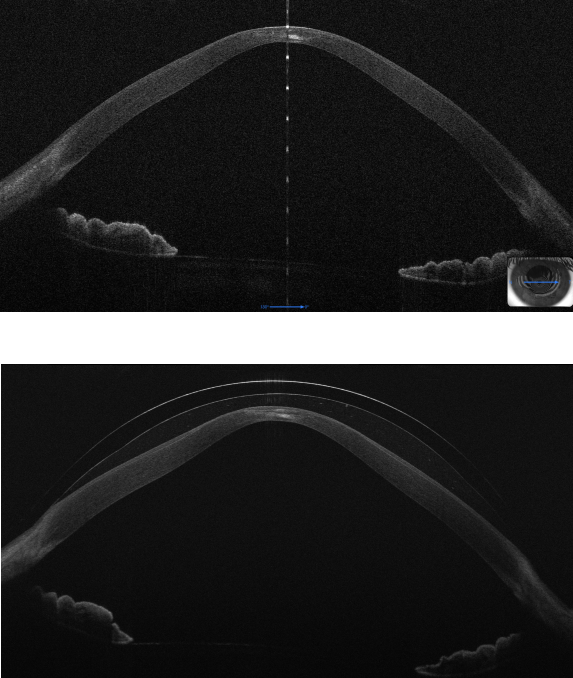

Il nostro protocollo applicativo , sviluppato nel corso di molti anni di attività professionale prevede l'utilizzo tecnologie innovative come la tomografia a coerenza ottica e la profilometria sclero corneale per offrire ai nostri utenti il massimo in termini progettazione e controllo delle lenti a contatto fornite .